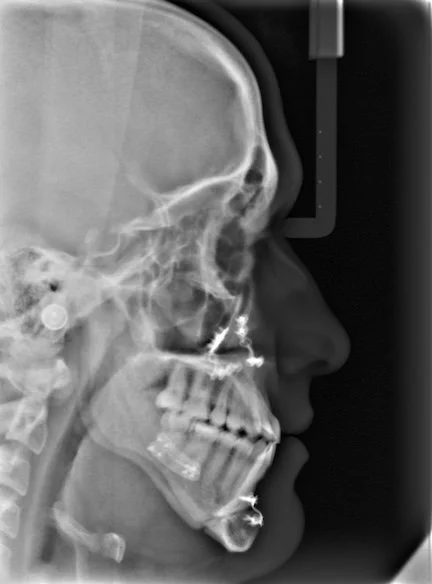

Lateral X-ray of a human skull showing teeth and jaw structure.

Most orthodontic concerns involve the teeth — their position, their alignment, the way they meet. These can almost always be addressed with braces or aligners alone. But some patients have a more fundamental issue: the jaws themselves don't fit together properly. In clinical terms, this is called a skeletal malocclusion — a bad bite caused not by tooth position alone, but by the size or position of the bones themselves.

When the underlying problem is skeletal, orthodontics alone has real limits. Straightening the teeth on jaws that don't fit together can improve appearance and alignment, and in some cases moving toward a better bite is possible — sometimes with the help of tooth extractions. But achieving a truly corrected bite when the skeletal relationship is significantly off requires moving the jaws themselves. That's where surgical orthodontics comes in.